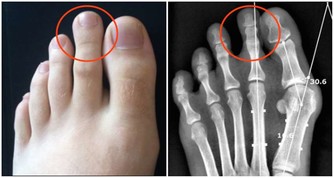

人的腳上有6條重要的經絡通過,通過腳的調節,虛弱的經絡就會感到酸痛,同時得到了鍛煉,經絡對應的髒腑和它循行的部位也就相應得到了調節。

這種方法可以使意念集中,將人體的氣血引向足底,對於高血壓、糖尿病、頸腰椎病等諸多疑難病都有立竿見影的療效,還可以治療小腦萎縮,並可預防美尼爾、痛風等許多病症。

對於足寒症更是效果奇佳,這是治本的方法,可以迅速地增強人體的免疫力。